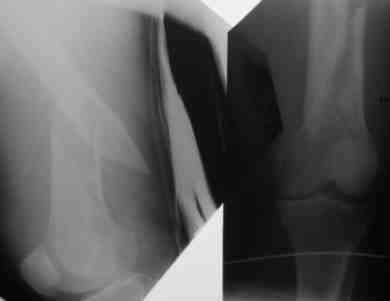

Он выпускается уже года 2, от UFN отличается дополнительым статическим отверстием на проксимальном конце, и возможностью ввести 4 винта: в 2 статических отверстия и по обоим краям овального.

На дистальном конце 2 статических отверстия, одно из них - передне-заднее, и овальное отверстие максимально дистально, в него можно ввести либо статический, либо динамический винты. Если ввести сразу 3 винта - они заклиниваются, создавая угловую стабильность.

Отверстия расположены более кучно. То есть гвоздь можно использовать не только при диафизарных, но и метафизарных переломах. Можно вводить и анте-, и ретроградно. При ретроградном варианте вверху запирать гвоздь удобнее через передне-заднее отверстие. Картинки в приложении.